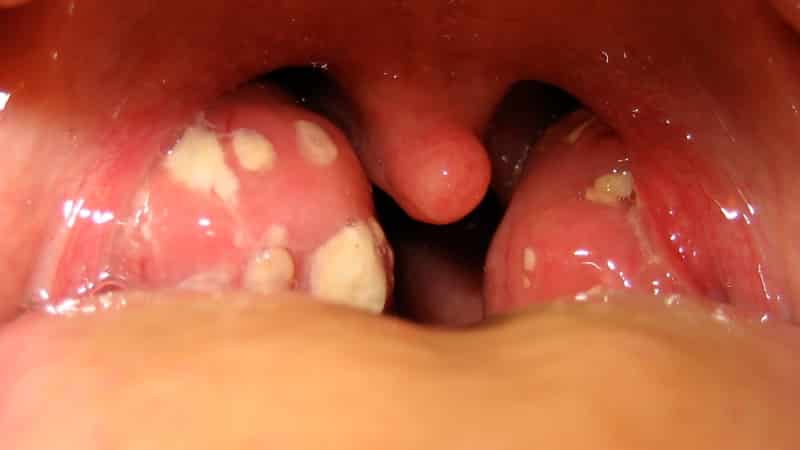

Острый и хронический тонзиллит. Это, пожалуй, самая распространенная причина появления белых точек на миндалинах. Заболевание представляет собой воспаление гланд, вызванное патологической микрофлорой. Острая гнойная форма характеризуется накоплением гноя в лакунах миндалин, что выглядит как плотные белые и желтоватые пробки, которые легко удаляются с помощью ватного тампона. Хроническая форма подразумевает постоянное наличие небольших пробок, которые нужно периодически удалять и полоскать горло. В этой форме, как правило, отсутствуют другие симптомы.

Если возникает ангина на фоне тонзиллита, у пациента наблюдается покраснение и воспаление горла, болезненность при разговоре и глотании, резкое повышение температуры, а гнойники увеличиваются в размере и становятся потенциальными источниками распространения инфекции по организму.

Плотные образования, которые мы наблюдаем в углублениях миндалин, имеют свою уникальную структуру. Обычно они состоят из мертвых клеток эпителия, мягкого зубного налета, остатков пищи, а также продуктов жизнедеятельности микробов и бактерий.

«Нормальные» комки могут быть как плотными и твердыми, так и рыхлыми и крошливыми. Обычно их размер не превышает 1 см, хотя иногда встречаются и более крупные образования.

Цвет этих бляшек может варьироваться – от чисто белого и сероватого до желтоватого, красного и светло-коричневого.

Появление таких образований на миндалинах не должно вызывать никаких симптомов или дискомфорта. Человек может заметить их только при визуальном осмотре горла. В некоторых случаях накопившиеся комки могут стать источником неприятного запаха изо рта, что связано с активностью микробов и бактерий, разложением остатков пищи и возможным нагноением. В таких ситуациях можно говорить о наличии хронического тонзиллита или повторяющихся болей в горле.